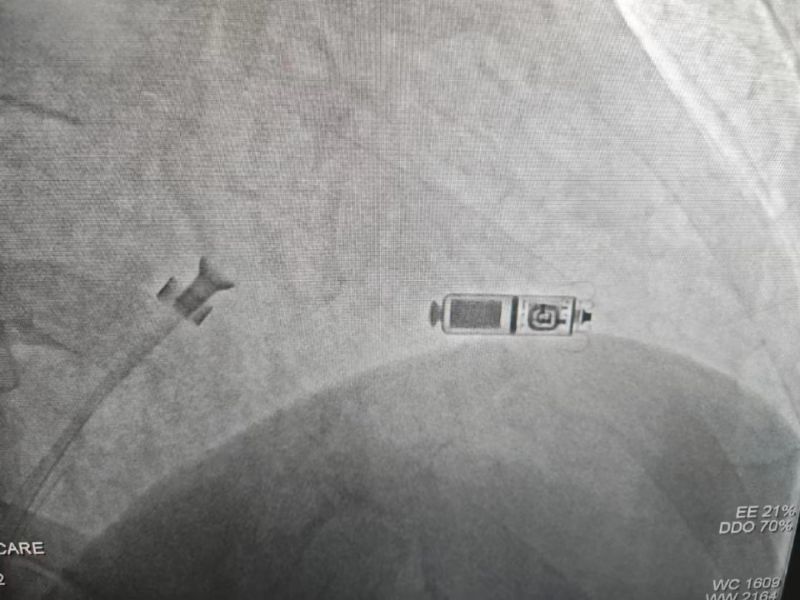

手術(shù)過程:經(jīng)過充分的術(shù)前討論,在延安大學(xué)咸陽醫(yī)院心血管病院吳棟梁院長、劉雄濤副院長的指導(dǎo)與支持下,李陽教授、何克強(qiáng)主治醫(yī)師、辛浩主治醫(yī)師與導(dǎo)管室介入團(tuán)隊(duì)的共同努力下,經(jīng)過超聲科、心電中心等多學(xué)科協(xié)作,成功為患者植入雙腔無導(dǎo)線永久起搏器,術(shù)后第二天患者在起搏器保障下經(jīng)藥物治療恢復(fù)正常的竇性心律。目前患者心臟情況及腦梗均恢復(fù)良好,已順利出院。

科普:Micra無導(dǎo)線起搏器號稱“世界最小起搏器”,無需植入心內(nèi)膜導(dǎo)線,也無需在胸前皮下制作囊袋放置脈沖發(fā)生器(起搏器),手術(shù)僅需局部麻醉,通過股靜脈穿刺,將起搏器經(jīng)導(dǎo)管植入心腔內(nèi),手術(shù)時(shí)間短,減少出血、血腫及感染風(fēng)險(xiǎn),術(shù)后恢復(fù)快,肢體活動不受限,無異物感。

優(yōu)勢:比傳統(tǒng)起搏器體積減少93%,體積更小,重量僅2g,類似一顆維生素膠囊;雖體積只有傳統(tǒng)起搏器十分之一,但其小小身體儲存大能量,續(xù)航時(shí)間超過12年,整個手術(shù)過程平均約30分鐘,植入成功率高,術(shù)后8-12小時(shí)即可下床活動,術(shù)后1-2天即可出院;兼容1.5T(特斯拉)/3.0T全身核磁共振掃描。滿足患者植入Micra之后疾病的診斷和治療需求。